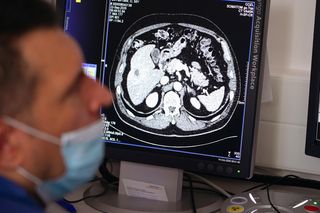

Ma wzrosnąć jakość leczenia i zwiększyć się dostęp do terapii pacjentów onkologicznych. Centrum Onkologii Ziemi Lubelskiej zakończyło gruntowną modernizację pracowni brachyterapii. Zakupiono wysokospecjalistyczny sprzęt i wyremontowano pomieszczenia za prawie 8,6 mln zł. To jedyna taka pracownia w województwie lubelskim.

- Według mojej wiedzy, to też jedyna pracownia w Polsce tak wyposażona. Został tam wymieniony tomograf. To jest taki tomograf, który umożliwia nam jednoczesne obrazowanie, w którym miejscu będziemy napromieniać. Pozwala to na bardzo precyzyjną radioterapię, która jest nakierowana wysoką dawką na małe, dobrze ograniczone, ale położone też niejednokrotnie w trudnych lokalizacjach struktury. Szczególnie tutaj mówię o brchyterapii przerzutów i nowotworów pierwotnych wątroby. My w naszej pracowni brachyterapii leczymy od nowotworów ginekologicznych poprzez nowotwory urologiczne, raka gruczołu krokowego, nowotwory w rejonie głowy i szyi, klatki piersiowej, nowotwory przełyku i jako pierwsi rozpoczęliśmy leczenie nowotworów wątroby i właśnie to leczenie jest takim dominującym - mówi dr Paweł Cisek, kierownik Pracowni Brachyterapii w Centrum Onkologii Ziemi Lubelskiej im. św. Jana z Dukli.

Brachyterapia jest metodą leczenia o wysokiej skuteczności miejscowej, porównywalną z innymi metodami niechirurgicznymi. Jej kluczową zaletą jest niska toksyczność i niewielka inwazyjność.​